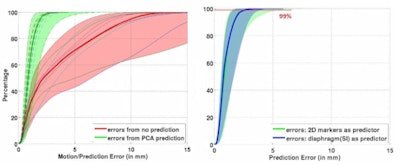

Left: PCA motion prediction using 2D fiducial markers. Right: PCA prediction using either tracked diaphragm SI-motion or 2D markers motion as predictor.

Left: PCA motion prediction using 2D fiducial markers. Right: PCA prediction using either tracked diaphragm SI-motion or 2D markers motion as predictor.The researchers examined the accuracy of their motion reconstruction by comparing the predicted results with the ground-truth motion (extracted directly from the 4D MRI data). Averaged over all 11 subjects, for 99% of predicted positions, median (maximum) errors were better than 2.63 (5.67) mm when tracking fiducial markers. Results were similar for tracking diaphragm motion, which resulted in a median (maximum) 99% prediction error of 2.7 (4.2) mm.

Comparing absolute dose differences between ground truth-based and prediction-based plans (using fiducial markers) showed that motion predictions from the translation-only scenario were poor, with maximum dose differences of more than 50%. Plans based on PCA-predicted motion, on the other hand, were similar to those based on ground-truth motion. Here, absolute dose differences of more than 5% occurred in only 3.61% (median) or 15.13% (maximum) of dose calculation points in the irradiated volume. Similar results were seen when tracking diaphragm motion.